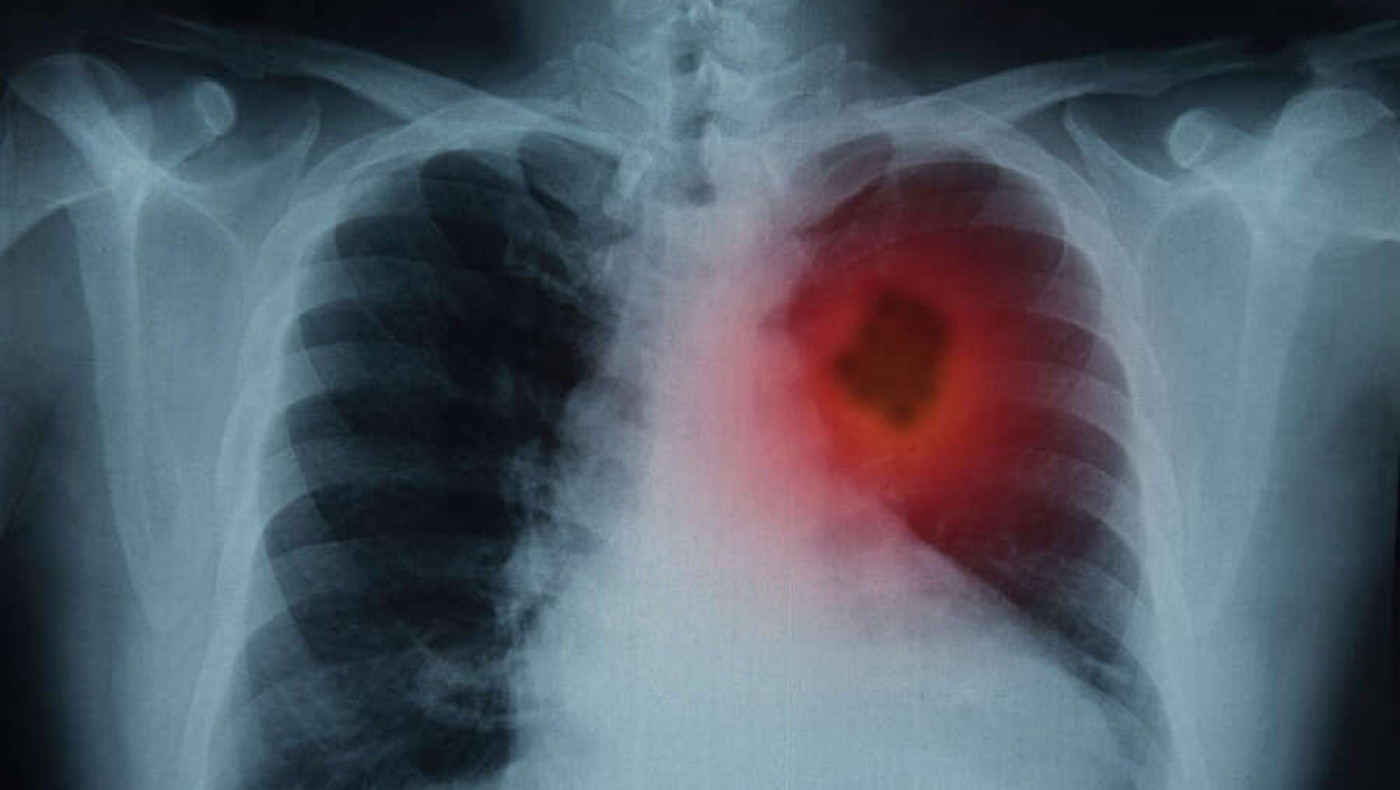

«Φρένο» στον πολλαπλασιασμό των καρκινικών κυττάρων στην περιοχή του πνεύμονα βάζει η βερβερίνη, μια φυσική ένωση που βρίσκεται σε μια ποικιλία βοτάνων όπως, ξαγκαθιά, γλυκαγκαθιά, τρικοκκιά, μπερβερίτσι, στoν θάμνο οξυάκανθα (Βερβερίς η κοινή, Berberis vulgaris, γνωστή και ως Ευρωπαϊκή οξυάκανθα) και στo βότανο υδραστίς η καναδική (Hydrastis Canadensis).

Σύμφωνα με νεότερη μελέτη που δημοσιεύτηκε στο Antioxidants, η φυσική ένωση κατέστειλλε τον πολλαπλασιασμό των καρκινικών κυττάρων του πνεύμονα στο εργαστήριο (in vitro), μειώνοντας παράλληλα τη φλεγμονή των αεραγωγών και τη βλάβη στα υγιή πνευμονικά κύτταρα που εκτίθενται σε χημικές ουσίες από τον καπνό του τσιγάρου.

Για να καθοριστούν οι αντικαρκινικοί μηχανισμοί που εμπλέκονται στη δράση της βερβερίνης, μετρήθηκαν τα επίπεδα του mRNA των γονιδίων που σχετίζονται με την εμφάνιση των όγκων και των επιπέδων έκφρασης της πρωτεΐνης. Διαπιστώθηκε ότι η βερβερίνη ρυθμίζει θετικά τα ογκοκατασταλτικά γονίδια και παράλληλα μειώνει τις πρωτεΐνες που εμπλέκονται στη μετακίνηση και τον πολλαπλασιασμό των καρκινικών κυττάρων. Επιπλέον, η βερβερίνη μπορεί και αναστέλλει το οξειδωτικό στρες, τη φλεγμονή και την κυτταρική γήρανση που προκαλείται από το εκχύλισμα καπνού του τσιγάρου, στα υγιή κύτταρα του πνεύμονα που αναπτύχθηκαν στο εργαστήριο.

Αξίζει να αναφερθεί, τέλος, ότι ο καρκίνος του πνεύμονα είναι είναι η κύρια αιτία θανάτων από καρκίνο παγκοσμίως, με περίπου 1,8 εκατομμύρια θανάτους να αναφέρονται ετησίως.